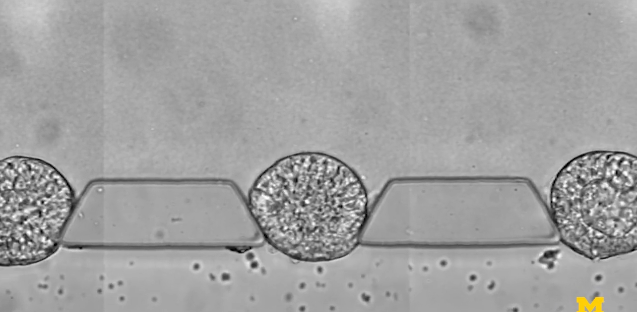

圖 | 微流控芯片的特寫(xiě)照片,該芯片幫助干細(xì)胞組織成胚胎樣結(jié)構(gòu),用于研究早期人類(lèi)發(fā)育(來(lái)源:Fu Lab, Michigan Engineering)

為了模擬胚胎著床后的發(fā)育階段,即羊膜囊開(kāi)始形成的時(shí)候,也是干細(xì)胞向分化成組織邁出第一步的時(shí)候,研究小組在一個(gè)可伸縮的三通道微流體系統(tǒng)中嘗試培育干細(xì)胞。中央通道包含一種模擬子宮壁的凝膠,兩側(cè)有一個(gè)通道用于為干細(xì)胞補(bǔ)充營(yíng)養(yǎng),另一個(gè)通道用于遞送引導(dǎo)。

研究人員由此開(kāi)發(fā)出來(lái)一種微流體裝置——由三個(gè)通道組成,分別用于放置細(xì)胞可嵌入的材料,裝載干細(xì)胞,以及輸運(yùn)刺激干細(xì)胞分化的因子,借此研究人員能夠控制干細(xì)胞在早期人類(lèi)胚胎中面向主要細(xì)胞譜系的分化,可以可靠地產(chǎn)生數(shù)百或數(shù)千種類(lèi)似胚胎的結(jié)構(gòu)。